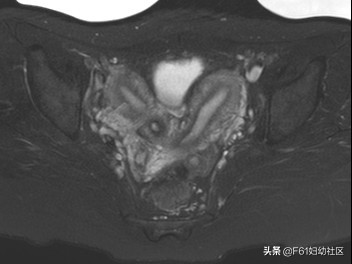

上图为子宫T2WI横断位,能看到两个宫体,子宫内膜增厚。

2、合并各种子宫畸形。其中双子宫最常见,MRI表现为双宫体、双宫颈,宫颈内分隔向下延续为阴道斜隔。